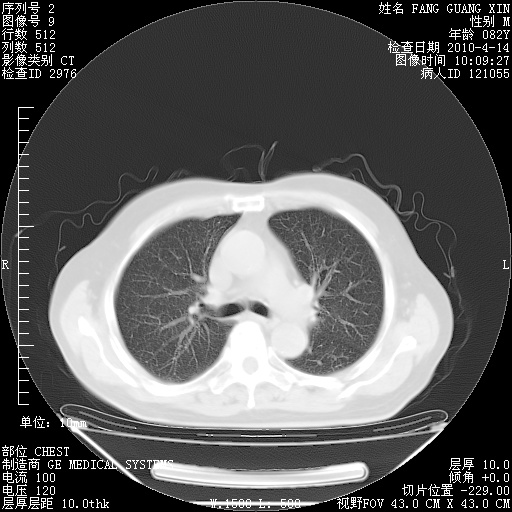

4月28日肺部CT——再次出现类似去年5月9日——透光度降低,(影像科认为)“间质性”改变。

4月28日肺部CT——再次出现类似去年5月9日——透光度降低,“间质性”改变。